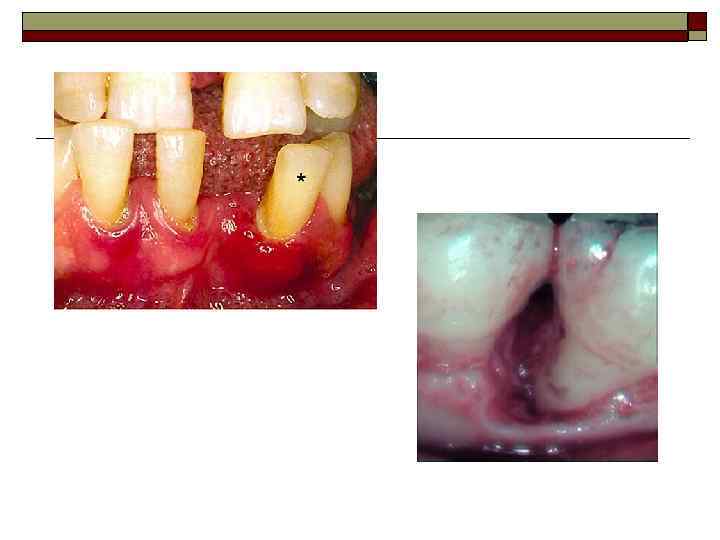

Классификация болезней пародонта I. Гингивит — воспаление десны, обусловленное неблагоприятным воздействием местных и общих факторов и протекающее без нарушения целостности зубодесневого прикрепления. Форма: катаральный, гипертрофический, язвенный. Тяжесть: легкая, средняя, тяжелая. Течение: острое, хроническое, обострение, ремиссия. Распространенность процесса: локализованный, генерализованный.

II. Пародонтит — воспаление тканей пародонта, характеризующееся прогрессирующей деструкцией периодонта и кости. Тяжесть: легкая, средняя, тяжелая. Течение: острое, хроническое, обострение (в том числе абсцедирование), ремиссия. Распространенность процесса: локализованный, генерализованный.